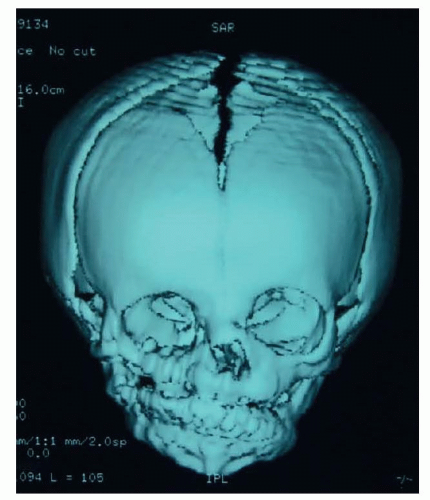

CT scanning is helpful to determine the extent of bony defect on orbital floor if the patient has severe orbital dystopia (FIG 6).

In the author’s center, cephalometric and panoramic radiographs and CT scans with 3D reconstruction are routinely recorded every 2 years from ages 5 to 17 years to monitor facial growth.